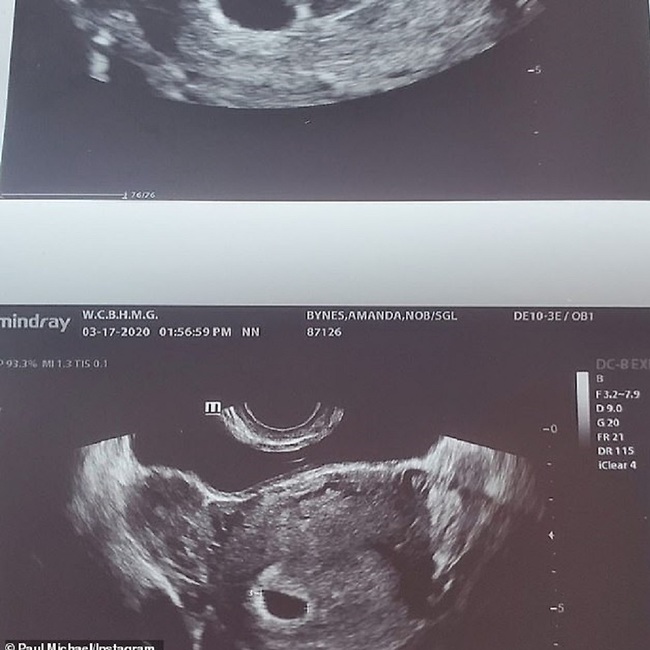

33-річна зірка фільмів «Відмінниця легкої поведінки» і «Лак для волосся» Аманда Байнс порадувала своїх шанувальників новиною про те, що скоро стане матір’ю. Вона і її наречений Пол Майкл сполохали Instagram, одночасно виклавши знімок УЗД.

«Дитина на борту», – підписала пост акторка. Але користувачі не встигли толком привітати пару, як публікації були поспішно видалені. З якої причини закохані вирішили видалити свої публікації, поки що не відомо, але інсайдери підтвердили новину про вагітність Байнс і відзначили, що дівчина неймовірно щаслива.